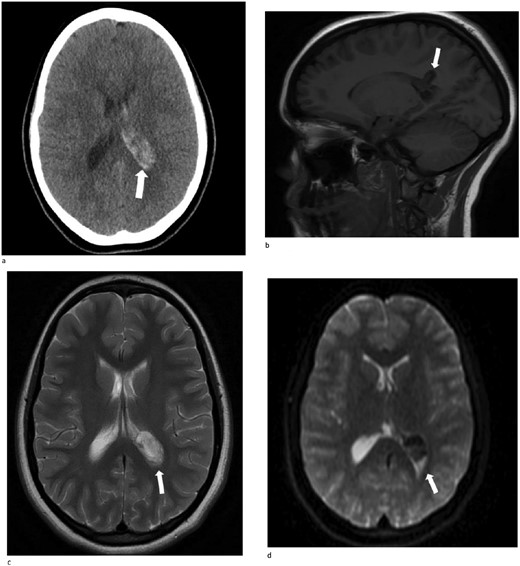

Only one small piece of the cystic lesion was obtained and entirely submitted for touch preparation and frozen section (Fig. 2), which demonstrated a hypercellular lesion composed of uniform ovoid cells with salt-and-pepper chromatin, lacking pleomorphism, grooves, nucleoli, increased mitotic activity, and had no papillary architecture. The intraventricular lesion was submitted separately and had the morphology of a benign papilloma (Fig. 3), staining with cytokeratin AE1/AE3, with no staining with GFAP. Because of the histological discrepancy of the first and second specimens, and the limited amount of tissue from the cystic lesion, the paraffin embedded tissue of the cystic lesion was submitted for methylation profiling by NIH. The methylation profiling had a maximum score of 1 for both class and subclass for EVN, WHO grade 2 (Fig. 4).

(a) and (b) The touch preparation and frozen section control shows similar histologic features. The cystic lesion shows a moderately hypercellular tumor, with uniform round nuclei, irregular distribution of chromatin, and a moderate amount of eosinophilic cytoplasm. There is no distinct fibrillary background (Hematoxylin and eosin, 400×).